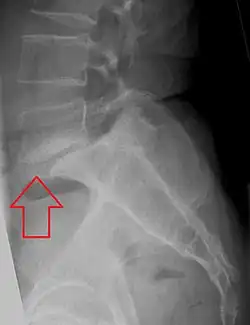

Spondylolisthesis

Spondylolisthesis is een rugaandoening waarbij de verbinding tussen twee wervels zodanig is verslapt of afwezig is dat de wervels zijn verschoven ten opzichte van elkaar, meestal op basis van een spondylolyse.

Patiënten hebben een overmatig holle rug (versterkte lordose) en lagerugklachten, meestal als het afglijden meer dan 25% is ten opzichte van de onderliggende wervel. Bij pijnklachten is het wenselijk om belastende activiteiten (zoals intensief sporten) te vermijden.